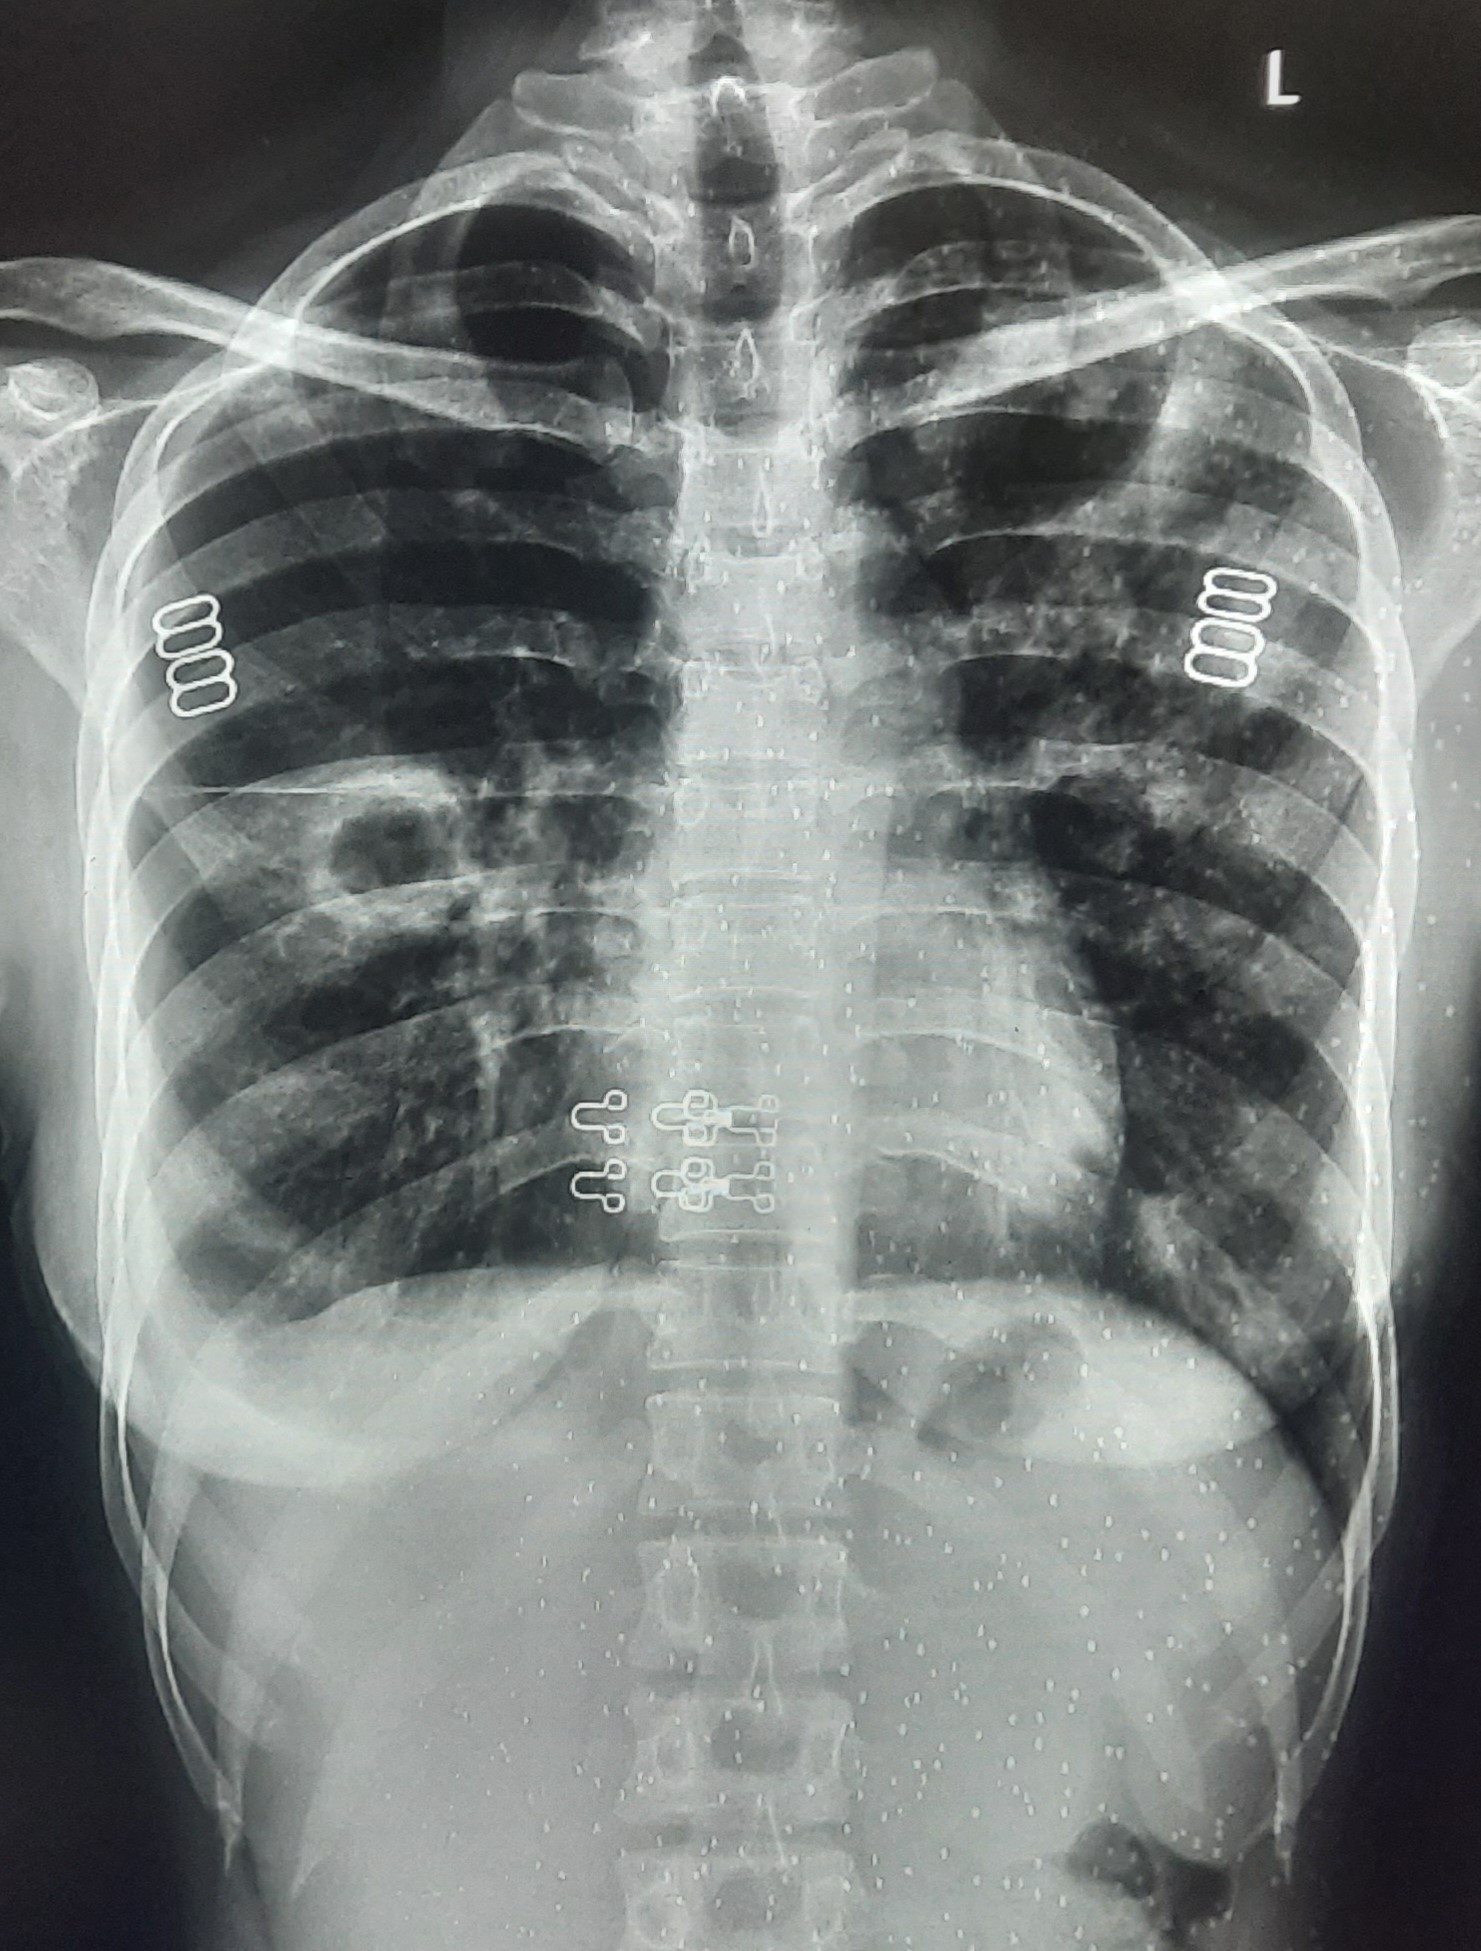

| 251 | IGGMC, Nagpur, Nagpur | P2 | 29-4221 | Ganpat Gaikawad | Consent taken on Paper | 70 Yrs. |

Provisional Diag : post TB sequele?

Final Diag : Fibrosis |

Non-TB Case (Confirmed) | Fibrosis | Abnormality visible on x-ray |